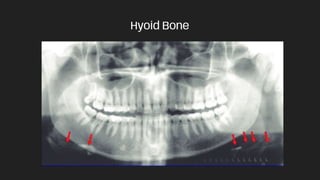

Hyoid Bone